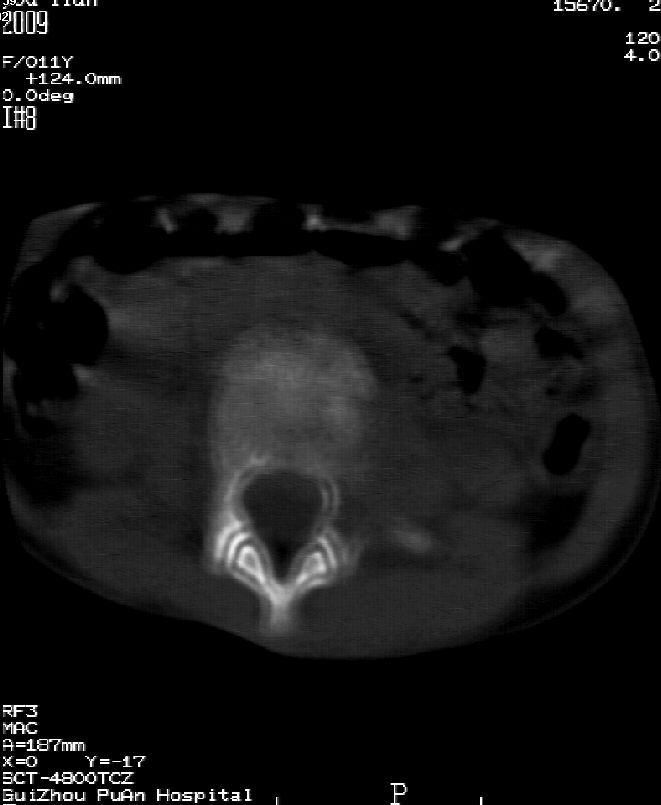

乍一看像是嗜酸性肉芽肿,但看到ct表现骨质破坏及软组织肿胀考虑结核可能性大,鉴别恶性肿瘤.

本例ct图像太不清楚了,而且不知道有没有传完,如果软组织病变只局限性于那几个层面的话多考虑嗜酸性肉芽肿,其次为其他肿瘤,结核椎旁软组织较广泛,在本例没有太典型表现,建议楼主(孩子父母吧)把所有的软组织窗图像(白色的那种)按顺序全部转上来.

考虑l3嗜酸性肉芽肿。